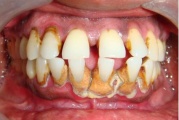

Krooniline parodontiit

Krooniline parodontiit on mikroobide poolt põhjustatud hammaste tugikudede põletik, mille tulemusena tekib progresseeruv alveolaarluu (nähtav röntgenograamil) ja periodontaalligamendi destruktsioon, igemetaskute moodustumine, igeme retsessioon või mõlemad kahjustused kombineeritult. Loe edasi »

- igemed veritsevad (19)

- igemed punetavad (21)

- ige on paistes (mädapunn)

- igemed on tursunud/vohavad (17)

- igemepiir on taandunud (3)

- luu destruktsioon (5)

- puudulik suuhügieen (5)

- igemepealne hambakivi (5)

- vahed hammaste vahel (5)

- halb hingeõhk / suu haiseb (12)